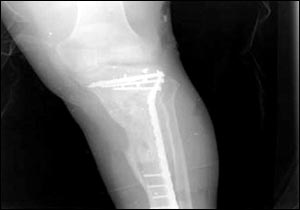

烏代傷腿的X光照片

7月24日,美國(guó)國(guó)防部通過(guò)由美國(guó)資助的伊拉克電視臺(tái)、兩家阿拉伯衛(wèi)星電視臺(tái)以及美國(guó)本土的CNN(有線(xiàn)新聞網(wǎng)絡(luò))將薩達(dá)姆的兩個(gè)兒子烏代和庫(kù)賽遭美軍擊斃慘死的照片公諸于世,同時(shí)被曝光的還有1996年烏代遇刺后所拍的傷腿的X光片。據(jù)悉,近60的伊拉克人收看這檔節(jié)目。此前,美軍中央司令部的里卡多·桑切斯中將在巴格達(dá)舉行新聞發(fā)布會(huì)時(shí)說(shuō),判斷烏代和庫(kù)賽被打死的依據(jù)是在現(xiàn)場(chǎng)發(fā)現(xiàn)的牙齒以及曾任薩達(dá)姆助手的目擊證人的指認(rèn)。